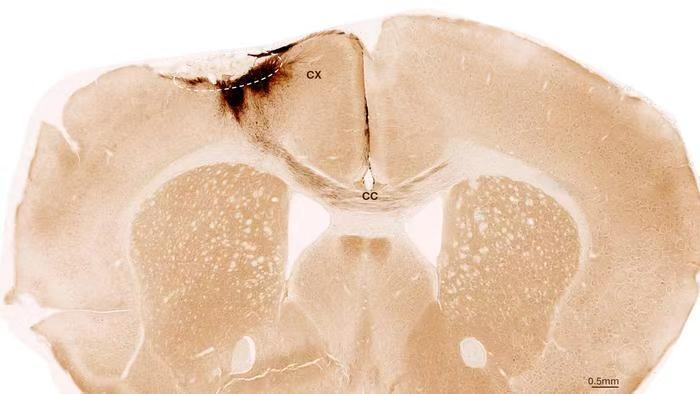

神经干细胞移植后小鼠大脑的冠状切面。虚线圆圈标示了中风区域。移植的人类细胞所发出的神经突起被染成深棕色。这些神经突起不仅向局部皮层(CX)延伸,还通过胼胝体(CC)延伸至另一侧大脑半球。图片来源:苏黎世大学